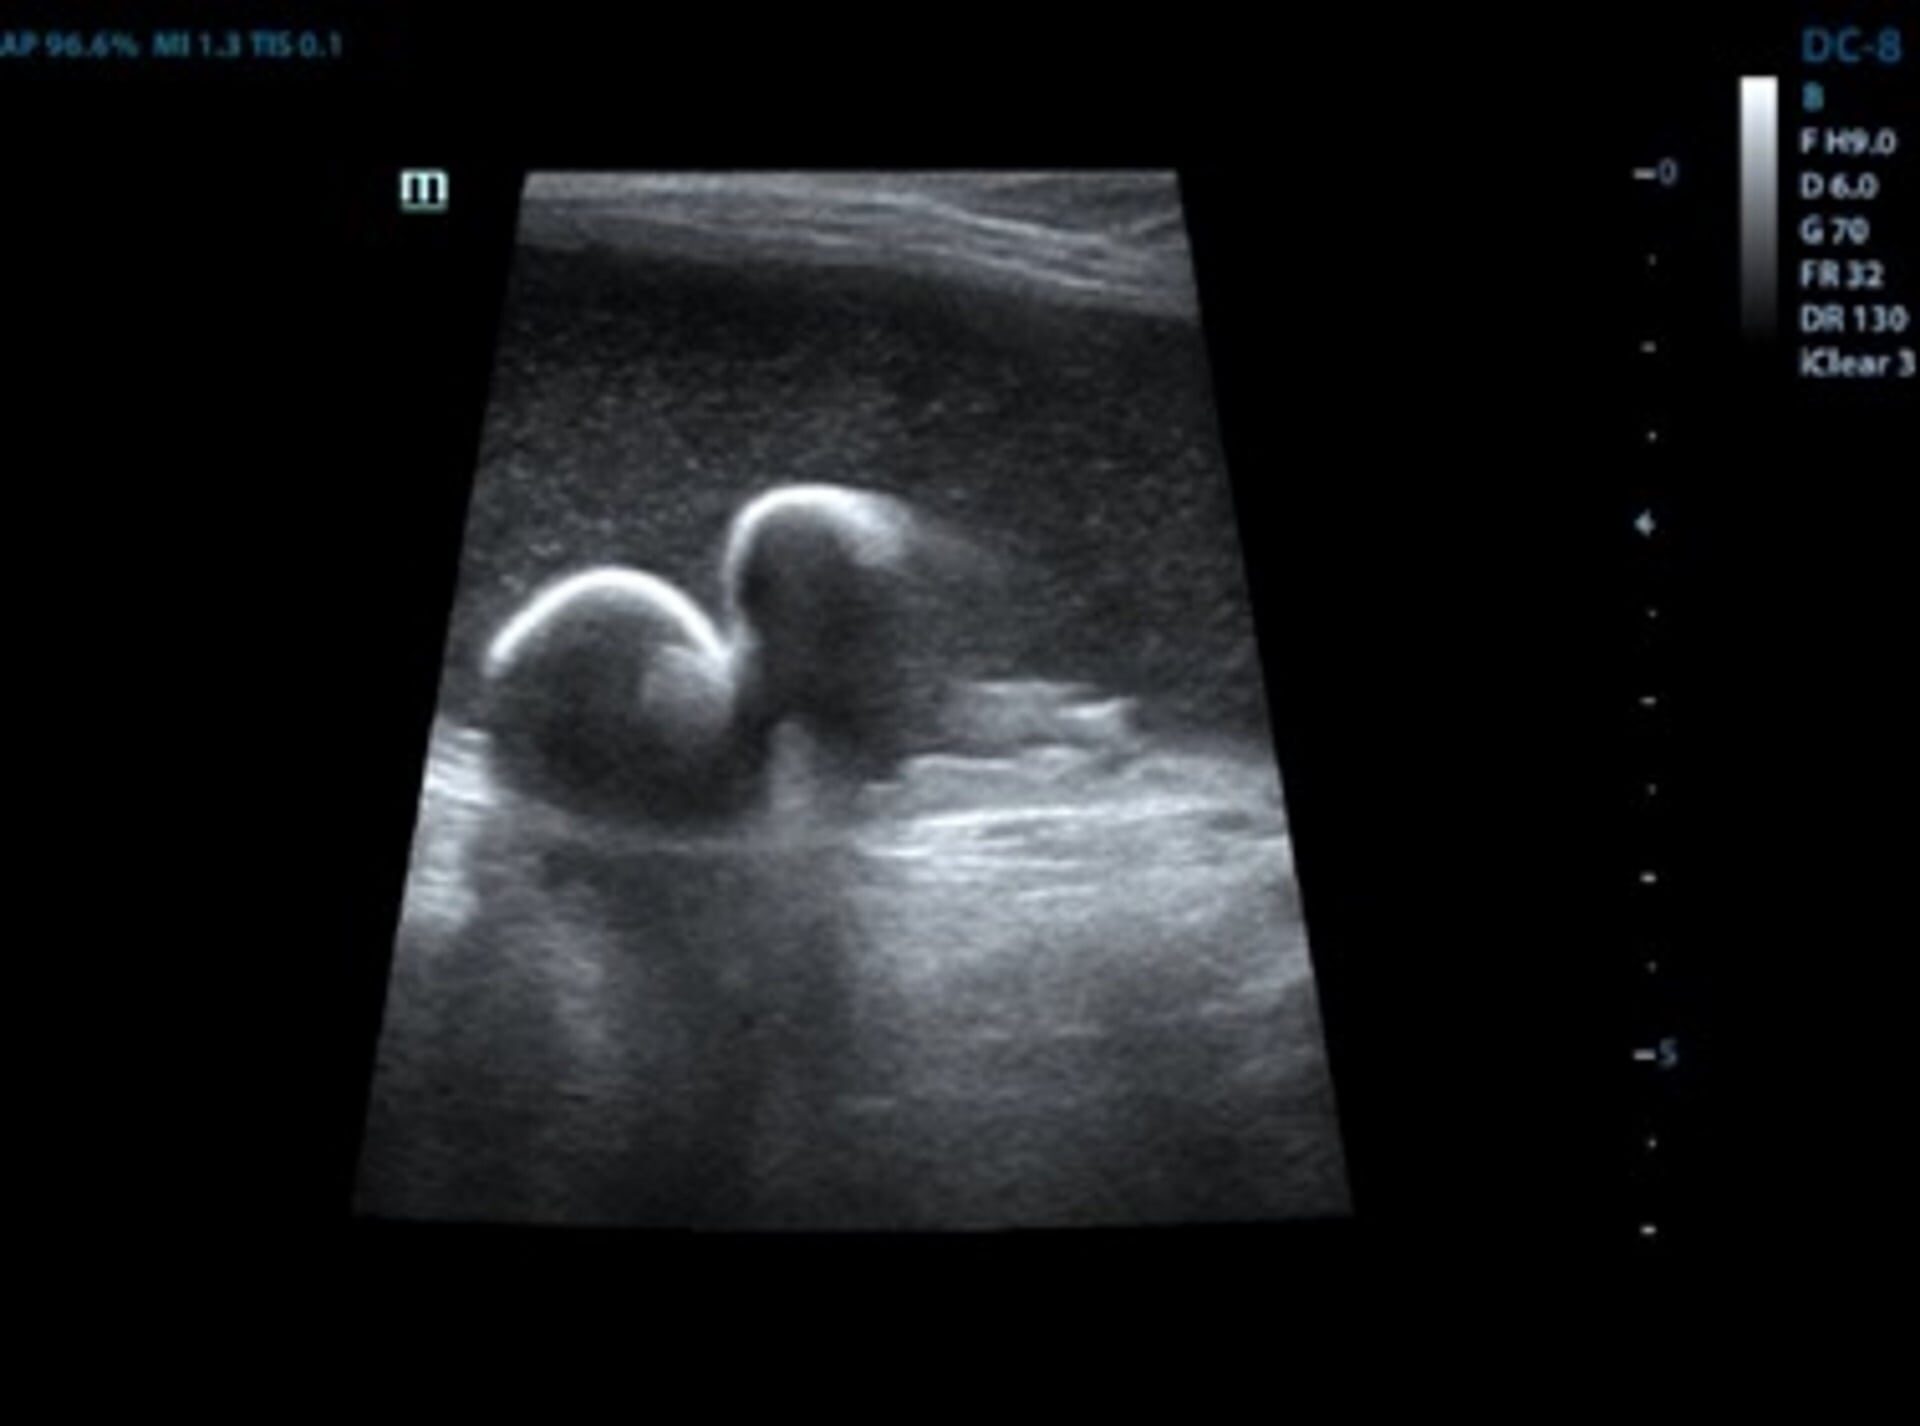

Как повысить уровень кальция в крови . 26 .12 .2019 admin Комментарии Нет комментариев . Сегодня рассматриваем ионизированный кальций,что это такое, что показывает,в чем разница с общим кальцием .

Что значит кальций ионизированный? Ионизированный кальций - это кальций, который свободно циркулирует в крови и не связан с белками .Поэтому его еще называют свободным кальцием . . * До начала исследования пробирка . . .

Как подготовиться к анализу на ионизированный кальций? Забор крови должен проводиться утром с восьми до одиннадцати часов . Кровь сдается натощак, после 14-часового голодания . Разрешается пить негазированную воду . За несколько дней до анализа требуется избегать переедания, употребления жирного, острого, жареного, спиртного и т .д .

Проводится анализ на содержание свободного кальция путем изучения пробы венозной крови . Сдается анализ строго натощак в утреннее время (до 11 часов) . Пациент должен правильно подготовиться к забору крови, необходимо: исключить прием алкоголя жирной и пряной пищи минимум за сутки до проведения процедуры;